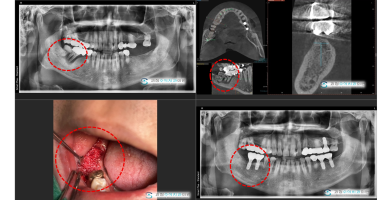

사랑니를 뽑아야하는 이유

보이시나요? 사랑니를 발치해보니 오랜기간 사용해야하는 큰 어금니가 사랑니의 영향으로 흡수가 되었어요....